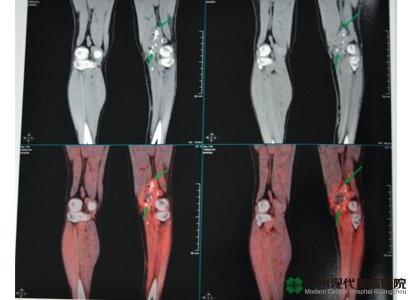

เนื้องอกในกล้ามเนื้อแข้ง

ในต้นปี 2012 โชคร้ายเข้ามาที่ตัวผมอีก คราวนี้ผมไม่ใช่คนโชคดีเหมือนแต่ก่อนแล้ว ผล MRIพบว่าเป็นเนื้องอกอยู่ในกล้ามเนื้อแข้งอีก เนื้องอกนั้นยังย้ายไปที่ปอดและมีอาการต่อมน้ำเหลืองบวม หมอบอกว่าอาการโรคของผมอยู่ระยะสุดท้ายแล้ว แนะนำให้ผมรักษาโดยตัดขา แต่การตัดขาหมายถึงผมต้องสูญเสียขาสองข้างของผมตลอดชีวิต ยังไงผมก็รับไม่ได้ ผมจึงปฏิเสธการรักษาโดยตัดขา และพยายามค้นหาวิธีการรักษาที่ทันสมัย หวังว่าจะได้รักษาขาสองข้างของผม

หลังผ่านการตรวจอย่างละเอียด ผู้เชี่ยวชาญของโรงพยาบาลมะเร็งสมัยใหม่กว่างโจวได้วางแผนการรักษาโดยใช้ความเย็น วิธีเซลล์ภูมิคุ้มกันบำบัดและวิธีเคมีบำบัดโดยอุดเส้นเลือดเฉพาะจุด คุณหมอบอกว่าวิธีการใช้ความเย็นรวมอยู่ในการรักษาแบบบาดแผลเล็ก ซึ่งก็คือ การใช้ความเย็นจากผิวหนังเจาะถึงเนื้องอกโดยตรงภายใต้การนำทางจากภาพถ่าย อุณหภูมิลดลงอย่างรวดเร็วทำให้เนื้องอกกลายเป็นลูกบอลน้ำแข็ง หลังจากนั้นก็ให้อุณหภูมิสูงขึ้นอย่างรวดเร็ว ลูกบอลนั้นจะละลายอย่างกะทันหันจนแตกในที่สุด เพื่อทำลายเนื้อเยื่อของเนื้องอก ทั้งหมดนี้จะดำเนินอยู่ในเนื้อเยื่อ ผมจะไม่มีความรู้สึกที่ไม่สบาย ซึ่งความจริงก็ได้พิสูจน์คำพูดของผมแล้ว

นี่เป็นครั้งที่ห้าที่ผมมารักษาที่โรงพยาบาลมะเร็งสมัยใหม่กว่างโจว บัดนี้เนื้องอกในกล้ามเนื้อแข้งเล็กลงไปตั้งเยอะ ต่อมน้ำเหลืองที่บวมอยู่นั้นก็หายไปแล้ว คุณหมอพูดกับผมว่า “ผมของคุณจะออกใหม่ในเร็ว ๆ นี้ค่ะ ” ซึ่งทำให้ผมรู้สึกมีกำลังใจยิ่งขึ้น และผมเชื่อมั่นว่า ถ้าผมพยายามมารักษาอย่างต่อเนื่อง วันที่ผมกลับไปตีกอล์ฟนับวันจะถึง